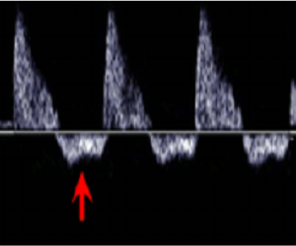

Neonatology Resistive Index 3 Image